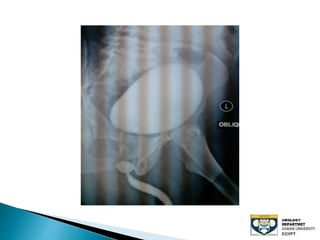

The document discusses urinary tract stones, detailing their types, causes, symptoms, and diagnostic methods. It highlights the risk factors such as infections and obstructions, with men being more commonly affected. Treatment options include various surgical methods, particularly for managing bladder outflow obstruction and lithiasis.